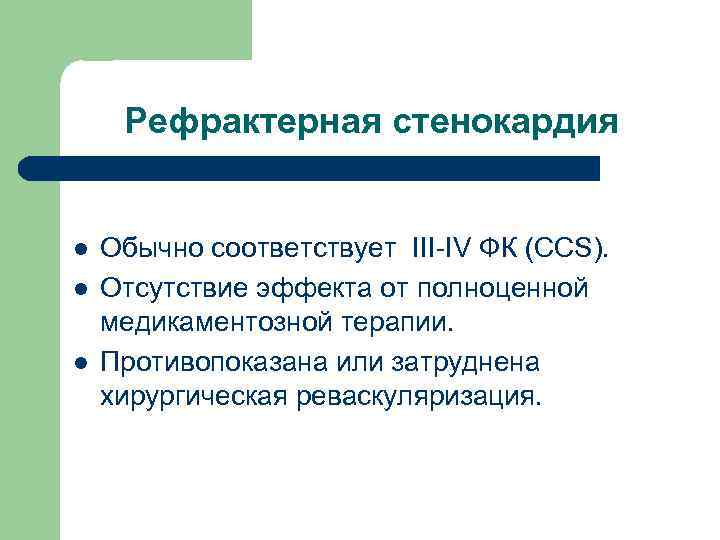

Рефрактерная стенокардия l l l Обычно соответствует III-IV ФК (ССS). Отсутствие эффекта от полноценной медикаментозной терапии. Противопоказана или затруднена хирургическая реваскуляризация.